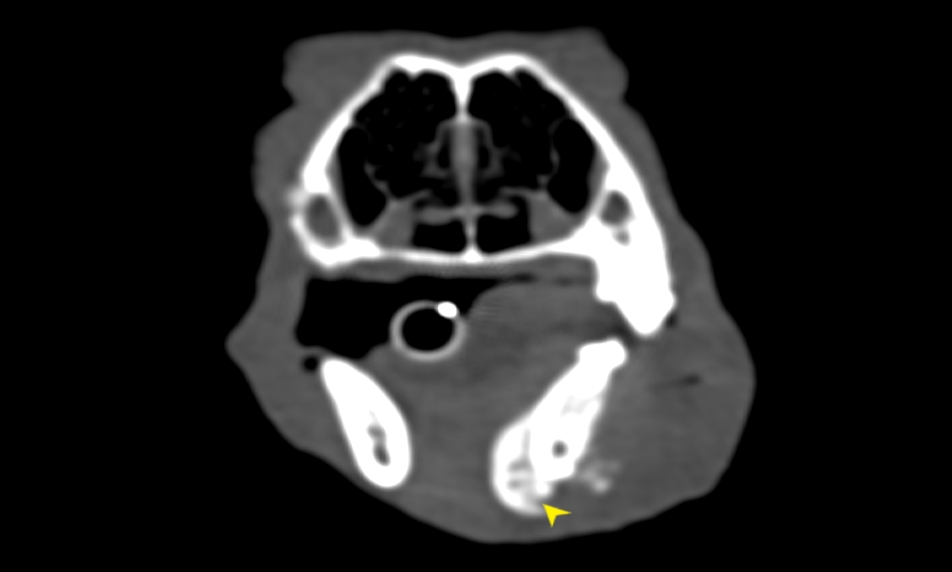

狗狗電腦斷層掃描 不明原因口腔出血 嚴重牙周病 口腔惡性腫瘤 鱗狀上皮細胞癌(Squamous cell carcinoma,SCC)

主訴嘴巴突然流血 口腔潰爛 左下顎腫脹 同時有嚴重牙周病 經由口腔採樣 電腦斷層掃描 確認為鱗狀上皮細胞癌(Squamous cell carcinoma,SCC)同時已經侵犯下顎骨。

確診後經由外科醫師、腫瘤科醫師、電腦斷層影像科醫師共同擬定治療計畫後

,大範圍切除左下顎,經過一年追蹤,目前狗狗一切安好喔。